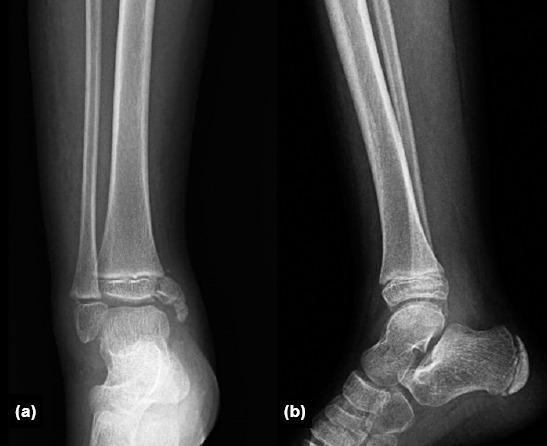

Background: Medial distal tibial Salter-Harris Type 3 and Type 4 epiphyseal injuries, also known as McFarland fractures, pose significant risks due to their potential to damage the growth plate and cause long-term joint deformities. Surgical treatment is commonly performed to restore joint congruity; however, there is no clear consensus on whether surgical or conservative treatment yields better outcomes. This study aimed to evaluate the mid-term clinical and radiological outcomes of surgical treatment in patients with McFarland fractures.

Methods: This retrospective study analyzed outcomes of 13 patients, aged 6-17 years, who underwent surgical treatment for McFarland fractures between 2021 and 2023 at a Level 1 Trauma Center. Surgical methods included screw fixation, K-wire fixation, and tension wire fixation. Outcome measures included radiological deformity assessments (lateral distal tibial angle [LDTA], anterior distal tibial angle [ADTA]), range of motion (ROM), Foot and Ankle Ability Measure (FAAM) scores for functional assessment, and Visual Analogue Scale (VAS) scores for pain. Comparisons were made between the operated and non-operated limbs.

Results: LDTA and ADTA values showed minimal differences between the operated and non-operated limbs, indicating successful surgical realignment (p<0.05). Although slight ROM limitations were observed in the operated limb, high FAAM scores and low VAS scores reflected good functional recovery and effective pain management. Correlation analysis revealed a moderate positive correlation (r=0.45) between FAAM scores and ROM, and a weaker correlation (r=0.32) between FAAM scores and radiological alignment.

Conclusion: Surgical treatment of McFarland fractures resulted in favorable clinical and radiological outcomes, with minimal limitations in ROM and significant improvements in alignment and functional recovery. However, ongoing follow-up is essential, particularly in younger patients, to monitor and manage the risk of potential growth disturbances.